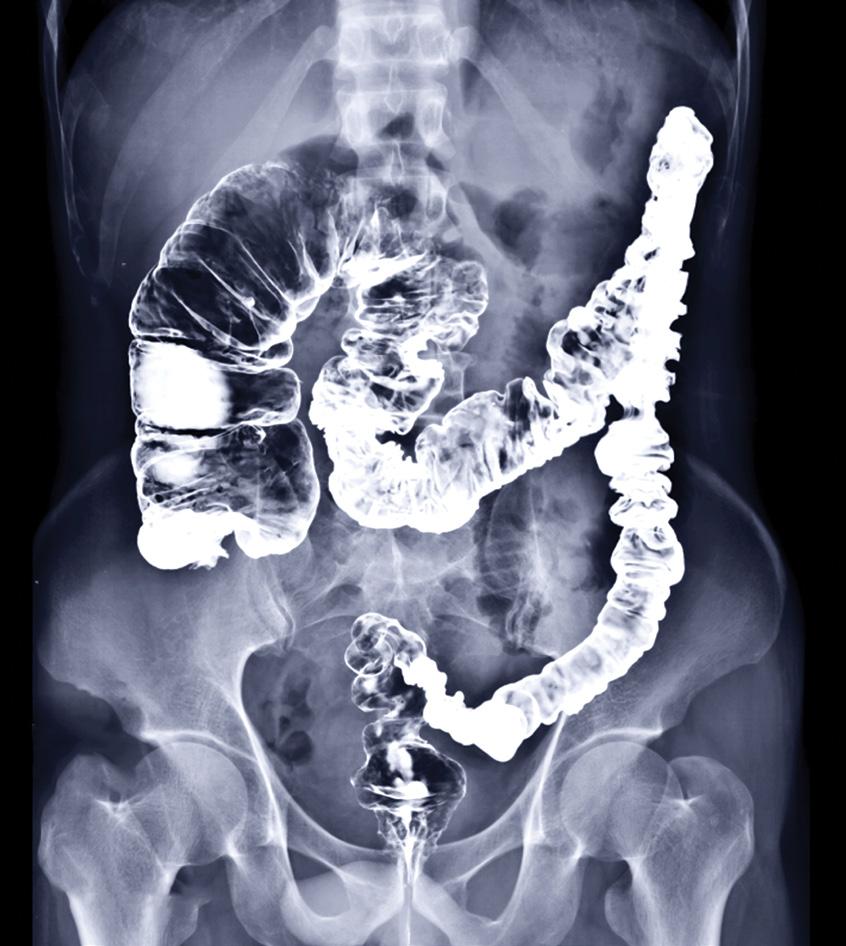

“The picture above is the large intestine (aka colon or bowel). It is highlighted in white from probably a barium x-ray procedure. In this x-ray you can see the beginning of the colon, the cecum and ascending colon are grossly expanded or herniated retaining fecal matter and sludge. This is happening because at the end of the bowel, (the descending and sigmoid colon) are so restricted that the fecal matter cannot get through and is literally backing up and expanding the previous parts of the colon. This leads to diverticulosis, diverticulitis, polyps, and eventually most likely colon-rectal cancer. Remember, according to medical texts, 100% of Americans will have some type of bowel disease by time they’re in their senior years.”